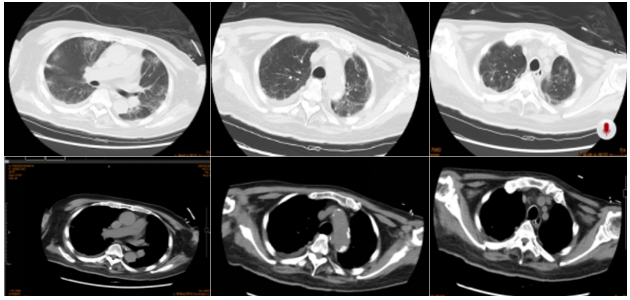

2025年3月4日胸部CT:双侧肺炎较前明显吸收,双侧少许胸腔积液3

3  患者胸部CT(2025-03-04)